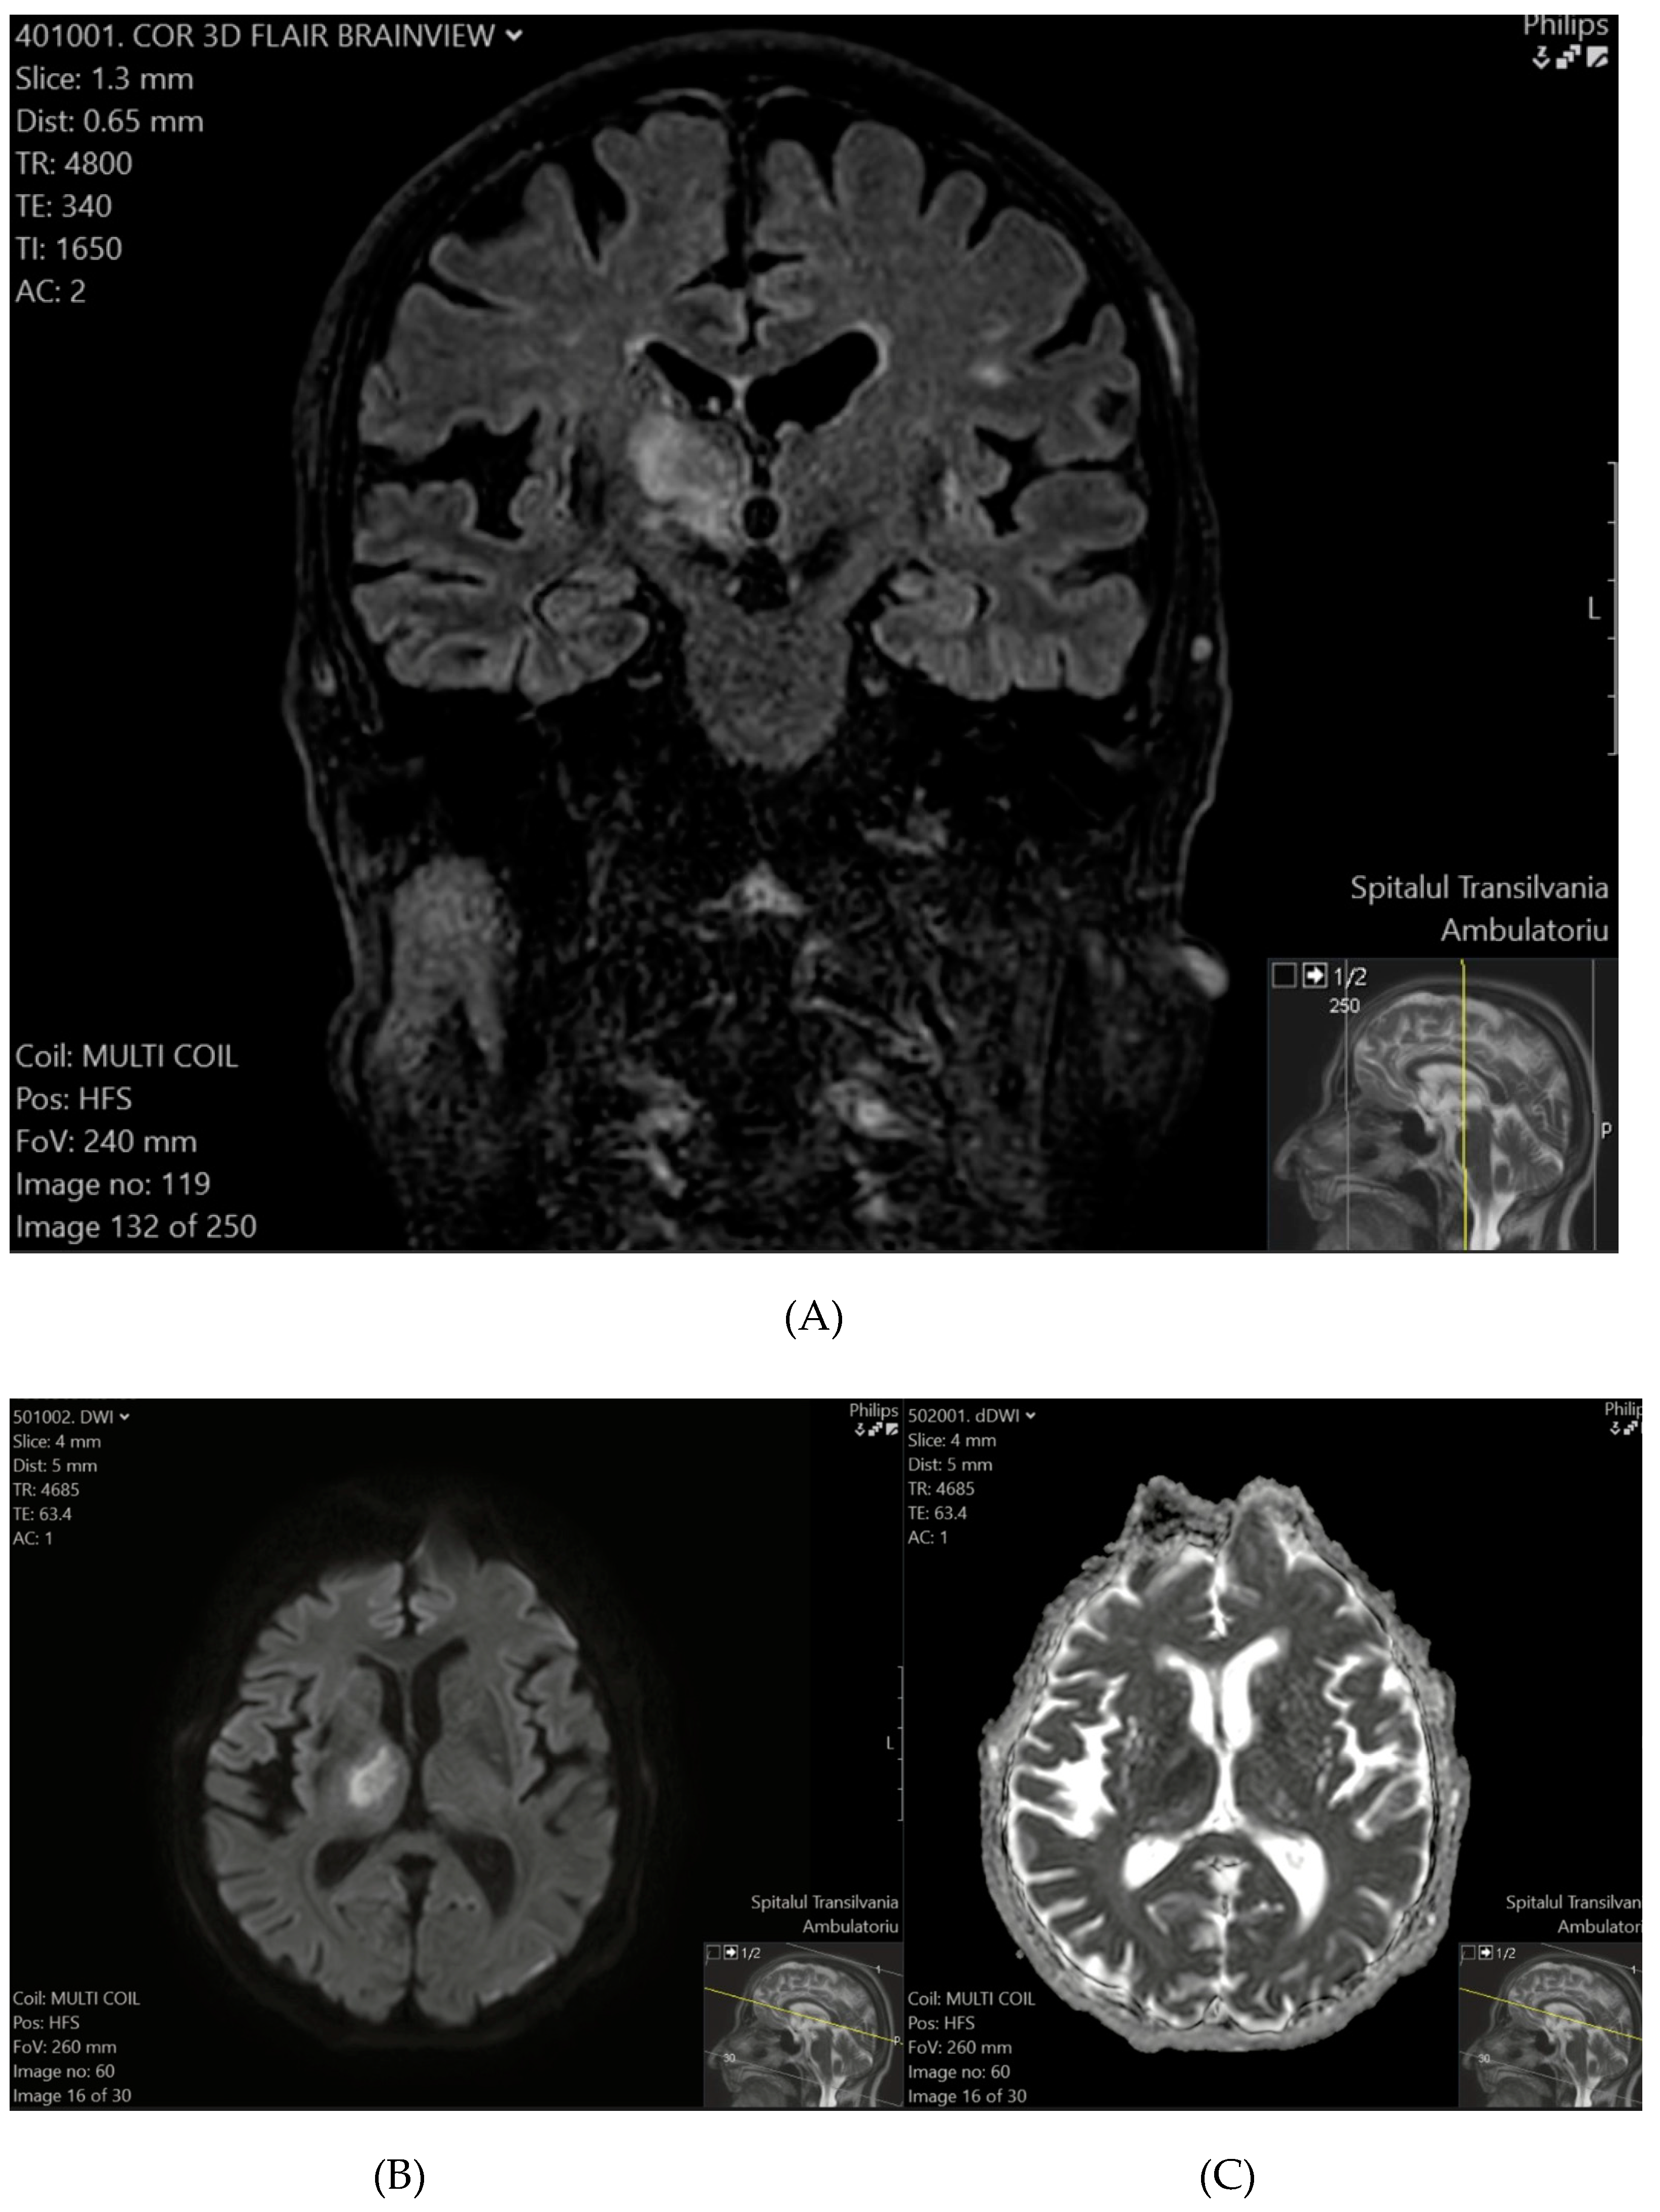

Ischemic lesions were identified in 26.92% of patients (95% CI: 11.6–47.8%), with a higher prevalence observed among older individuals, males, and those with a history of hypertension. These findings suggest that nearly one in four patients in the study cohort showed evidence of ischemic lesions, highlighting the importance of incorporating advanced imaging techniques to detect such lesions and understand their clinical significance in targeted patient subgroups. Representative MRI images from two patients illustrate characteristic ischemic lesions identified in our study cohort (Figure 1 and Figure 2). In Patient 1, a hyperintense lesion was observed in the right medulla oblongata on T2-FLAIR (Figure 1A), with corresponding diffusion restriction on DWI (Figure 1B) and a hypointense ADC signal (Figure 1C), confirming acute ischemia.

Figure 1. (A) (top) T2-FLAIR sequence reveals a hyperintense focus on the right side of the medulla oblongata. (B) (bottom-left) DWI confirms an ischemic event, demonstrating diffusion restriction with a hyperintense signal. (C) (bottom-right) The corresponding ADC map shows a hypointense signal, further supporting the presence of acute ischemia.